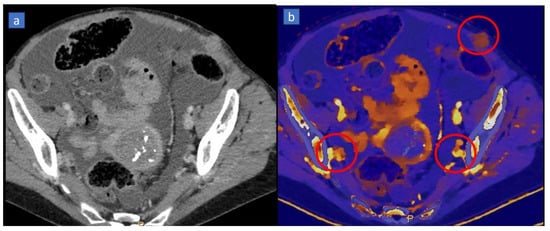

5. Bone Marrow Edema